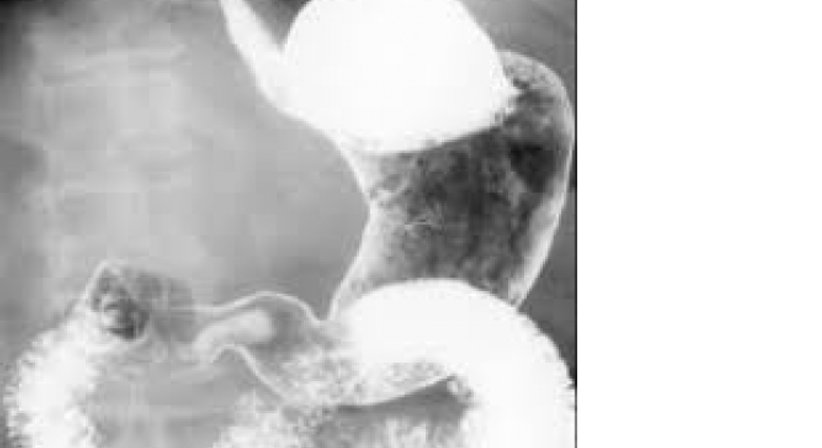

Im Rahmen von Röntgenuntersuchungen können durch die Verabreichung spezieller Kontrastmittel Innere Organe untersucht werden.

Für die Untersuchungen des Magens wird Kontrastmittel getrunken, für den Dickdarm wird ein Kontrasmitteleinlauf vorgenommen.